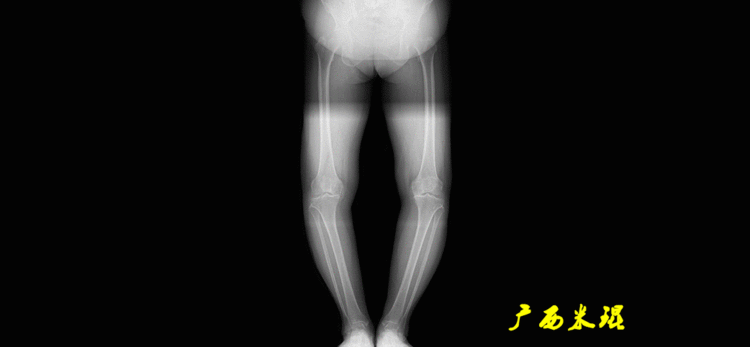

下肢力线及相关角度测量的前提是必须拍摄标准的站立位也就是负重位的下肢全长片。目前这样的照片都是放射科的技师在电脑上拼接出来的,大部分医院的DR都能够做到这一点。

患者直立于摄影架上,后背贴近摄影架,双手自然下垂,膝关节尽量伸直,足部与双肩同宽,要求投照时双髌骨朝正前方,通常患者双足尖应平行向前即可。

提醒一下大家,拍摄过程中应避免下肢的外旋和内旋。如果有一侧肢体短缩时,投照应当用脚垫垫高短缩肢体,使骨盆保持水平,这样下肢短缩测量才精确。如果有肢体旋转畸形时,还是以髌骨朝前为标准,虽然此时双足可能不能保持平行。

二、下肢全长片的基本要求

无论如何,拍摄出来的下肢全长片必须包含髋关节中心、膝关节中心及踝关节中心,否则对临床是无用的。有了一张下肢的全长照片,我们需要确定下肢关节的中心点,通过中心点画出下肢的各种轴线,然后利用轴线与关节线的相交得出各种所需要的角度。